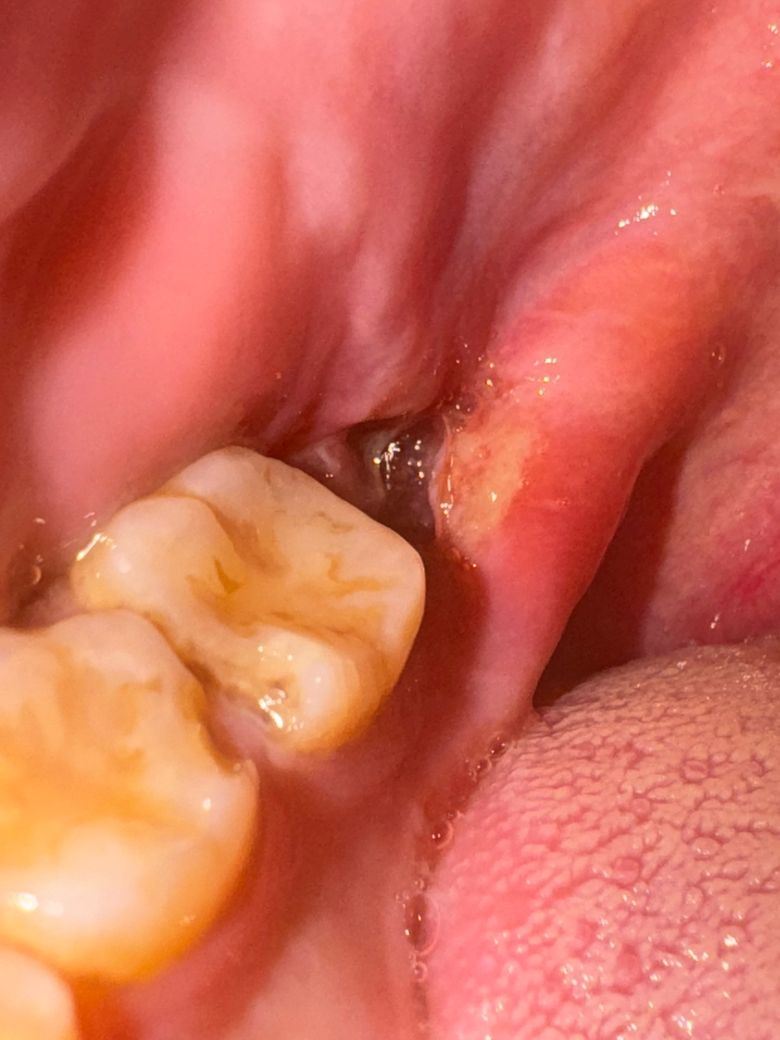

사랑니 발치 3일차, 자고 일어났는데 약간 통증이 있어요

혹시 혈병이 빠지거나 한건가요? 1일차는 좀 통증이 있었고 2일차는 통증 없이 지났는데 3일차인 오늘 일어나니 턱까지 욱신거리는것과 시린 통증이 좀 있네요. 사진상으로도 혈병이 약간 빠진게 아닌가 싶어서 불안합니다.

• 1번 째 사진

사랑니 발치 후에는 일주일 정도 까지는 통증이 느껴질 수 있습니다. 사진상 별 문제 없어보입니다.

사진상으로는 지혈도 잘되신거 같습니다. 아직 상처가 다 아물지 않아서 자극이 가게되면 통증이 생길수도 있습니다.

사진으로 봤을 경우에는 혈병이 제거된 것으로 보이진 않습니다. 발치를 하고 나면 발치한 부위에 상처가 있기 때문에 통증이 있을 수 있습니다. 이런 경우 발치한 부위를 자극하지 않는다면 통증이 점차 줄어들게 됩니다.